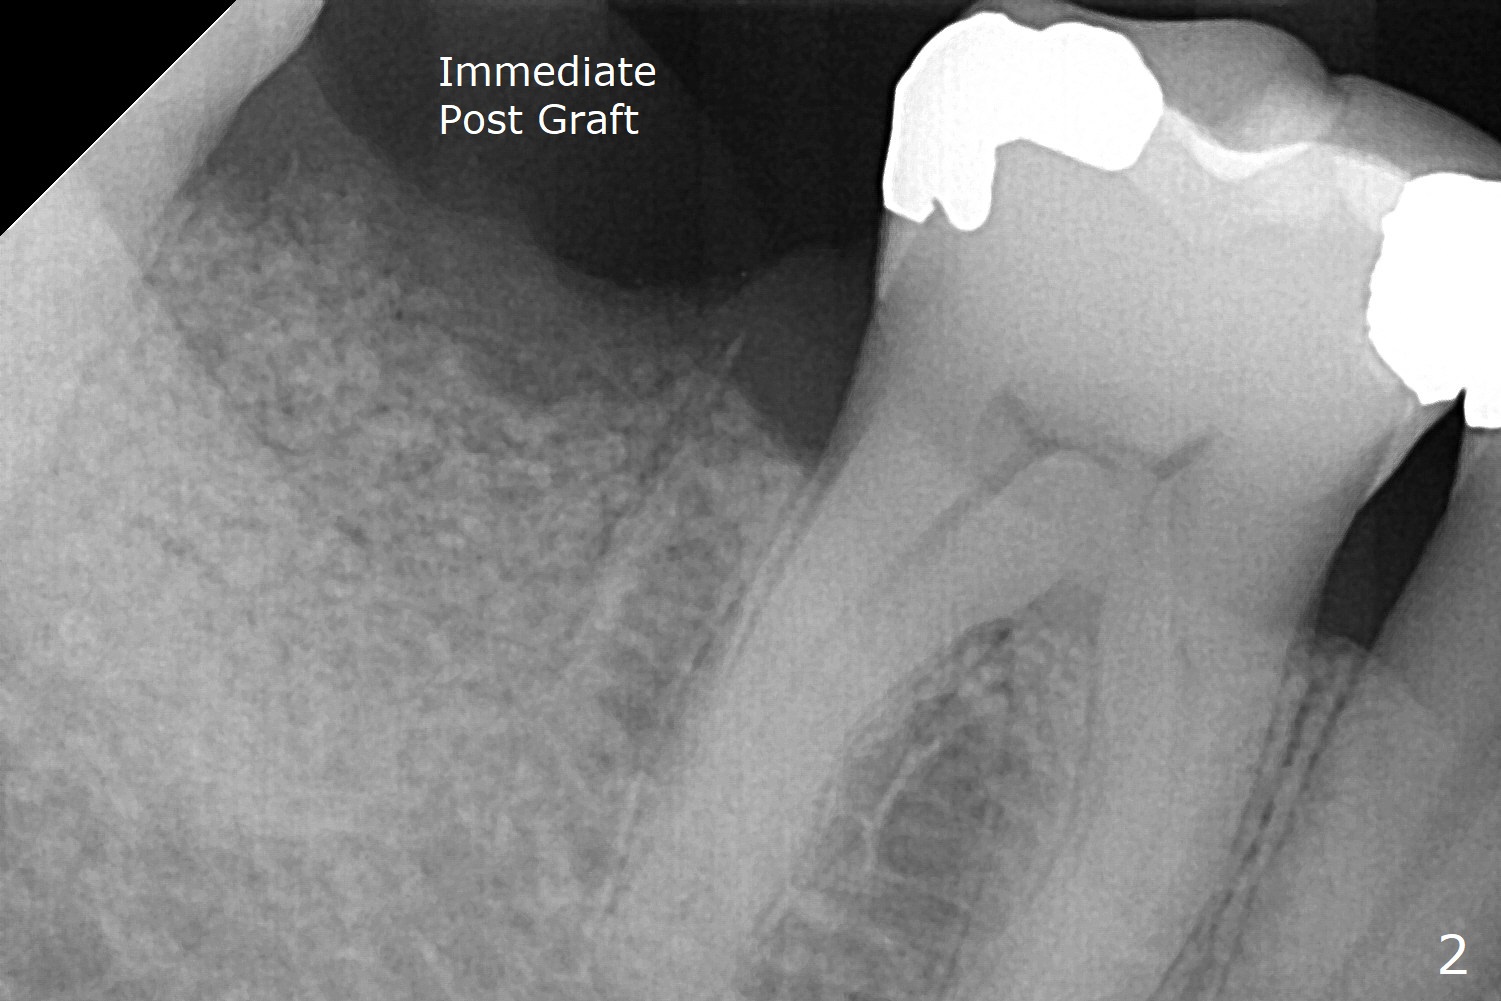

In fact the buccal gingival recession at #31 is asso-ciated with cervical caries perfor-ation (Fig.1 P). The debrided socket is packed with mine-ralized cortical: cance-llous mix (50:50) (better using mine-ralized cortical allograft (future particle size: 125μm – 850μm)) hydrated with ~ .25 ml of .3 mg/ml of rhPDGF-BB (one compo-nent of GEM21S, Fig.2,3). It is extremely difficult to close the socket opening with buccal defect with Osteogen Plug, 12x12 mm BioXclude and 4-0 PGA suture (Fig.4). Acrylic dressing is unstable in spite of several reline (Fig.5 A). Its replace-ment is GEM Cap RCM (regenerative collagen membrane), 9-12 month resorption time, which will be fixed in place with Perio Glue. Watch Video. In fact, 2 pieces of the reline dislodge in the 1st 2 days postop, while the whole piece 3rd days postop. The patient feels better when the acrylic dressing is out. It appears that the bone graft does not fall out, according to phone visit during coronavirus outbreak. A third method to close the buccal defect is to make mesial and distal release incisions (Fig.6) and transfer the flaps (Fig.7). In fact the bone graft gets lost, revealed over phone. Immediate implant is the most secure method to keep the bone graft. PRF may be more retentive. The fourth way is to place Cytoplast, which is fixed with spacer and periodontal dressing.